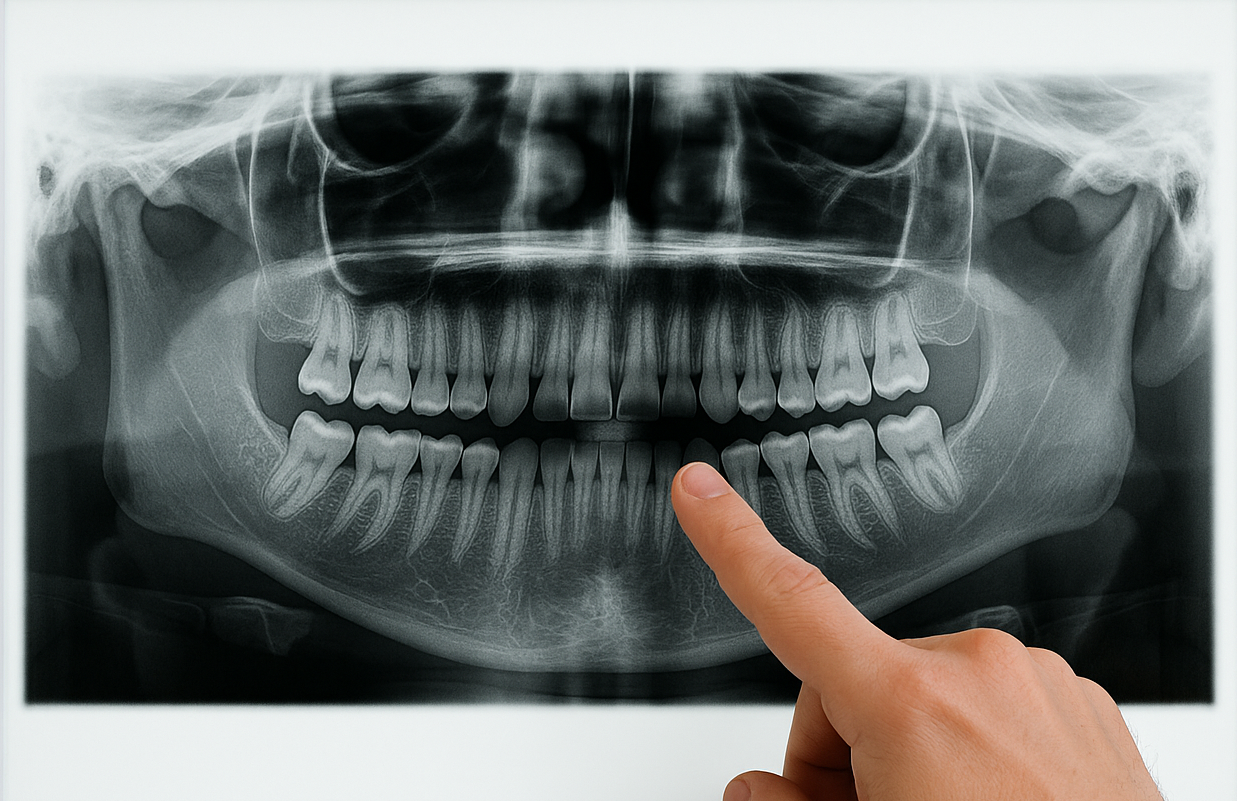

Implantes Dentários com Excelência,

no Coração de Pirituba.

Oferecemos implantes dentários, tratamentos completos e um ambiente seguro e confortável para você e sua família.

Mais de Duas Décadas de Dedicação à Sua Saúde Bucal

A Aqui Odontologia nasceu em 2003, fundada pelo Dr. Stefano Simão, que desde o início se dedica com paixão à odontologia. Movido pelo desejo de transformar vidas por meio do sorriso, ele criou uma clínica voltada para um atendimento humano, de qualidade e acessível.